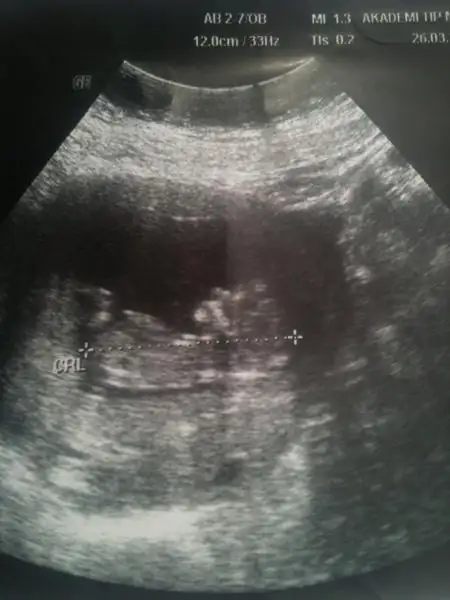

$241.webp $239.webp

bu da benim minik ORKİDEM yorum bekliyorum..yalnız eşim bilgisayarı akşam işe götürecek..saat 3 e kadar bakıcam inşallah o zamana kadar yorum yaparsın... ama yarın ilk iş buraya bakıcam..ORKİDEM yorumunu dört gözle bekliyorum.

burda 11hafta 6 günlük dayanamadım gittim. eşim hemen cinsiyeti sordu.dr a.dr dikişlerimden sezeryan olduğumu anladı ilk çocuğu sordu kız deyince kıyafetlerini attınız mı dedi hayır dedik bu da kız dedi.yani kız gibi görünüyo.dedi..pipisi çok küçükse onu bilemem.ama 15 gün sonra gelin daha kesin konuşurum dedi...

canim dr un kiz demis ama ilki kiz gibi ikinci resimm ise bariz erkekk